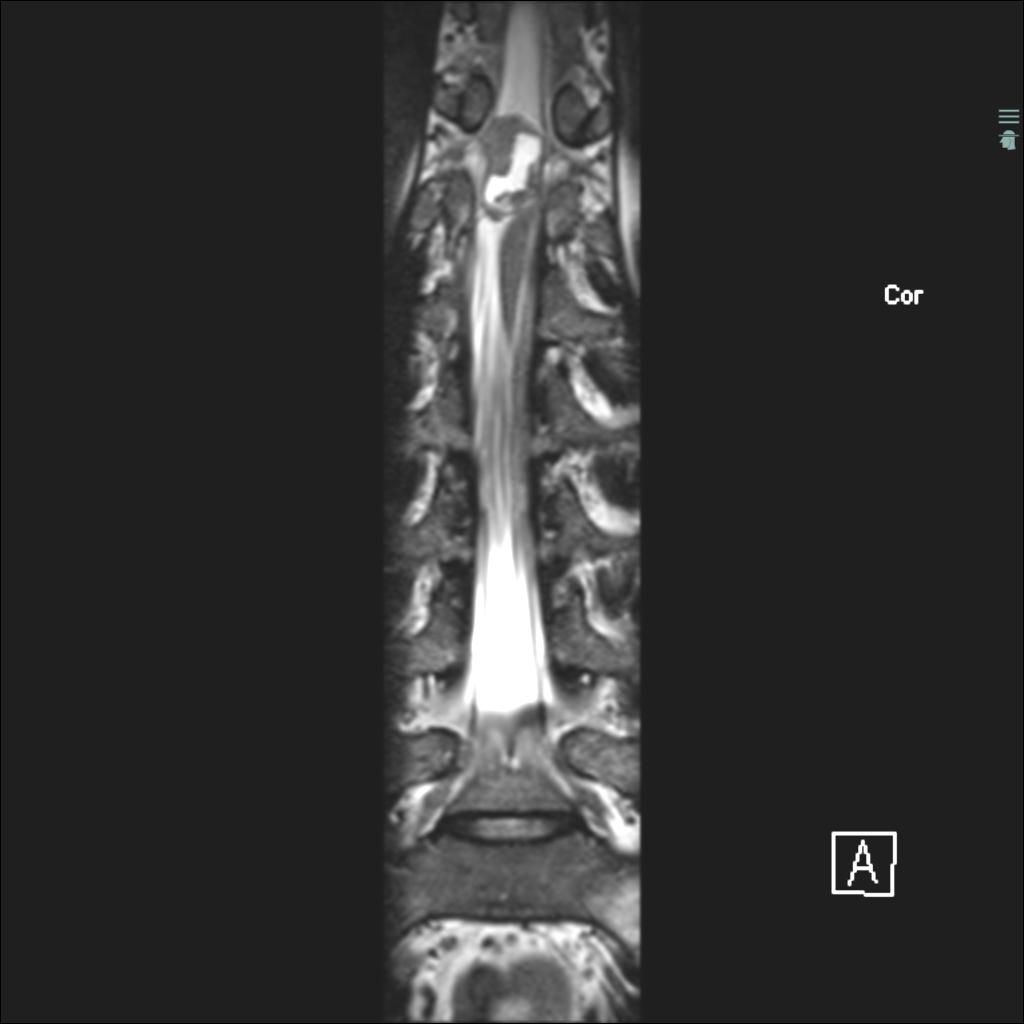

Case History: 40-year-old man with low back pain, right lower extremity paraesthesias, and incontinence. He presents 10 days later with worsening pain.

What is your diagnosis?